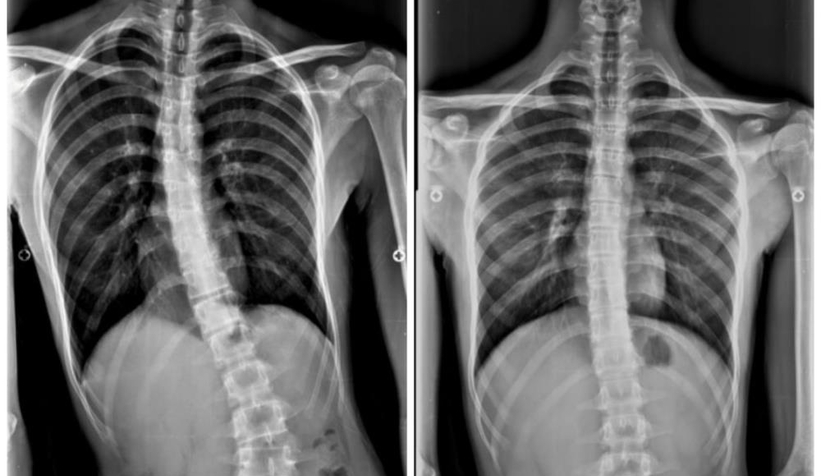

Umudunu kaybetmek üzere olan genç, son olarak Sakarya Eğitim ve Araştırma Hastanesi'nde görev yapan Doç. Dr. Alauddin Kochai’ye başvurdu. Doç. Dr. Alauddin Kochai’nin yaptığı muayene sonrasında tüm tetkikleri yeniden yapılan 16 yaşındaki Aziz Koray Diş’e Osteoid Osteoma ismi verilen kemiğin iyi huylu tümörü teşhisi konuldu.

Aziz Koray Diş’in sosyal hayatını da etkileyecek dereceye gelen eğriliğinin tespiti sonrasında hızlıca tedavi sürecine geçildiğini belirten Sakarya Eğitim ve Araştırma Hastanesi Ortopedi ve Travmatoloji Bölümü'nde görevli Doç. Dr. Alauddin Kochai, “Aziz’in bize geldiğinde ciddi bir eğriliği vardı ve bu eğriliğin kaynağı bir türlü bulunamamıştı. Burada gerekli tetkikleri yaparak bu eğriliğin iyi huylu tümör olduğunu belirledik ve buna yönelik yaptığımız cerrahi sonrasında sağlığına kavuştu ve 2 ay içerisinde tamamen sağlığına kavuştu” dedi.